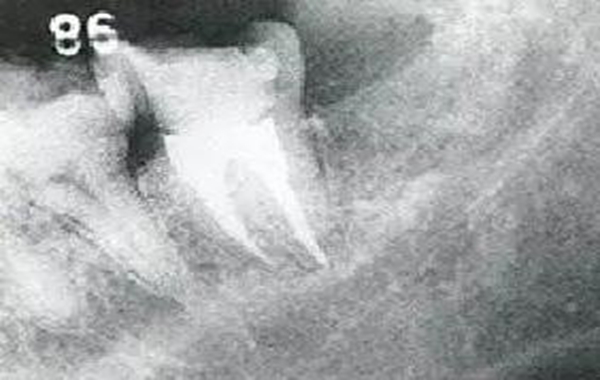

●智齒拔牙引起的附著喪失

27歲的女性,下頜左側(cè)智齒冠周炎引起腫脹而來(lái)院的患者。左下7的遠(yuǎn)中與智齒牙冠部相連的地方有6mm的牙周袋,并伴有出血和排膿。

智齒拔牙2個(gè)月后的狀態(tài),由于拔牙是的左下7的遠(yuǎn)中牙槽骨大量缺損。

智齒拔牙14個(gè)月后的狀態(tài)。X片上可觀察到,左下7遠(yuǎn)中側(cè)牙槽骨再生。但是仍然存在6mm的牙周袋和牙周出血。